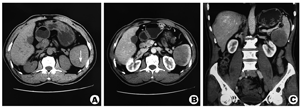

患者,男,59岁,因体检B超发现脾脏占位于2017年7月23日入本院肝胆外科。患者无自觉不适症状,既往有糖尿病病史,曾因腹股沟疝和消化道溃疡穿孔行手术治疗。查体未发现阳性体征。检验血常规:白细胞3.39×109/L,血小板75×109/L,淋巴细胞0.85×109/L,均稍低于正常下限,血清肿瘤标记物正常。肿物在B超描述:稍增强回声,内见点条状血流信号。CT检测:平扫稍低密度类圆形肿块,边界不清,增强扫描动脉期不均匀强化,强化程度低于脾脏,7.5 cm×5.7 cm×5.5 cm(图1)。CT诊断意见:淋巴瘤、不典型血管瘤或血管淋巴瘤。PET-CT:氟脱氧葡萄糖(FDG)代谢稍高,最大标准摄取值(SUXmax)2.99,倾向良性肿瘤。

PSA缺乏特异临床表现,多数患者可出现腹部不适等一些非特异性表现。约10%表现出恶性肿瘤警示征:不明原因发热、乏力、体重减轻等,约30%因脾自发破裂就诊。实验室检查同样缺乏特异性,常有贫血、血小板减少,也可能观察到血小板增多、白细胞增多,血沉加快等。超声、CT、MRI等检查都可能发现脾脏的异常,但很难同脾脏的其他良性或恶性肿瘤鉴别。CT具有相对较高的诊断效能,在平扫时可以发现增大的脾脏,内有高密度或低密度结节,增强时结节不均匀强化,有时可以发现大量钙化点[4]。PET-CT在鉴别良恶性上有一定帮助,SUXmax>6需高度怀疑恶性肿瘤。此患者在术前未准确诊断,这也说明影像学在诊断PSA上存在较大局限性。此外,回顾患者入院前1年体检时的CT平扫,在脾脏下极已经能够发现可疑病灶(图3),但被CT诊断所忽视。所幸疾病未发生质变,这说明影像医生对于脾脏肿瘤的认识和重视还需提升。其最终的诊断需依赖病理学检查,但不推荐活检,因为存在出血及肿瘤破裂播散的风险。